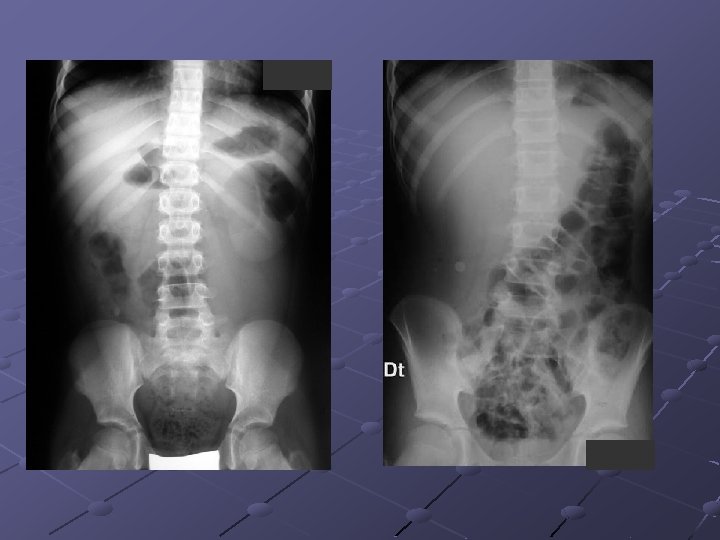

Cas n° 4 Garçon de 14 ans Porteur d’une maladie de Crohn Admis pour une poussée Pendant l’hospitalisation exacerbation des douleurs et distension abdominale

Mégacolon toxique Complication la + sévère des MII: col. ulcérative (1, 6 -13%), Crohn, Behcet, col. pseudomembraneuse amibiases, typhoïde, choléra Inflammat. suraiguë transmurale séreuse: perforation et/ou exsudation avec péritonite